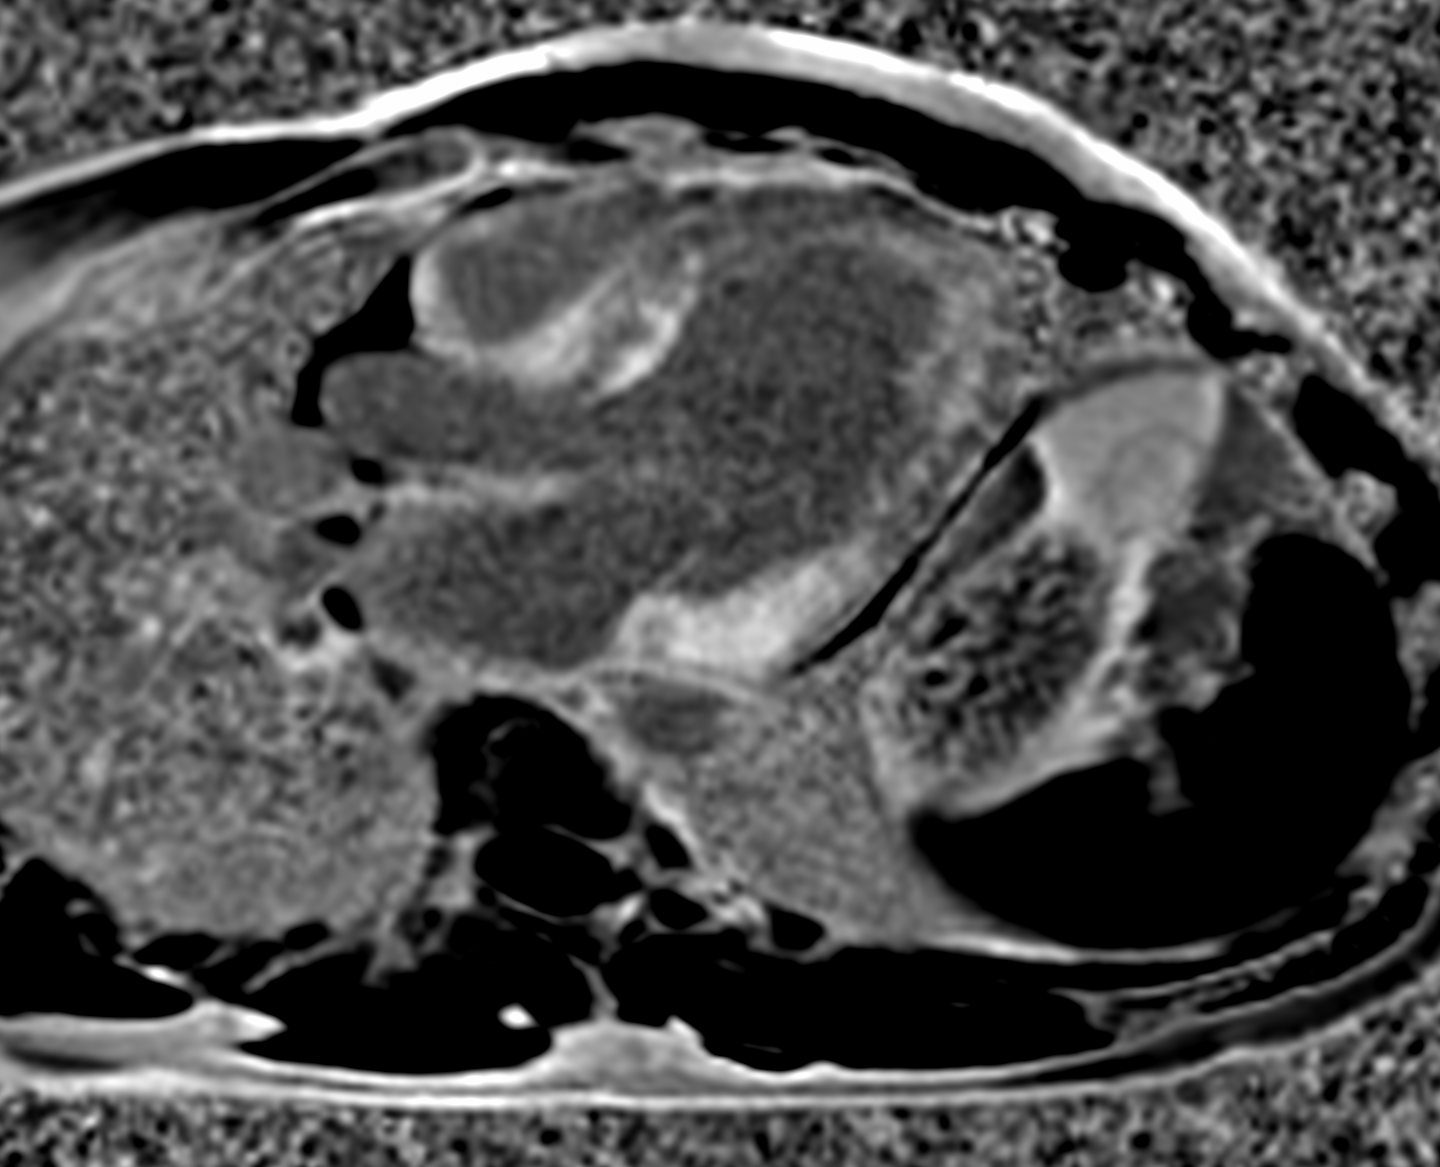

Recherche d’argument scintigraphique en faveur d’une amyloïdose cardiaque chez un patient de 44 ans hospitalisé dans le cadre d’un bilan de syncope d’effort avec suspicion d’amyloïdose à l’IRM réalisée le 07 avril 2021 objectivait une hypertrophie myocardique touchant préférentiellement les régions septale et inféro-latérale avec une hypokinésie globale du ventricule gauche (FEVG estimée à 40%). Contexte familial évocateur.

Hyperfixation intense et diffuse du radiotraceur à tropisme osseux au niveau du muscle cardiaque, avec une extinction de la fixation physiologique squelettique, et notamment des côtes (ratio H/CL = 2.6; score de Perugini = 3).

En l’absence de protéines circulantes (chaînes légères d’immunoglobulines), anomalies scintigraphiques évocatrices d’une amyloïdose cardiaque de forme ATTR (score de Perugini = 3).